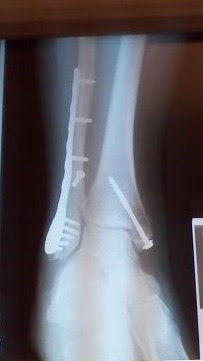

The laws of physics being what they are, I knew I had broken both them and my ankle as I flew head over heels down the hill. I was half right. I broke my ankle and leg.

I was in a wheelchair and then walker for twelve weeks. We lived in a three story house. You can see the predicament, right?